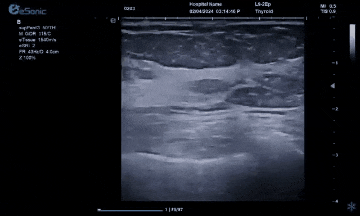

hjc888黄金城官网医疗(ESI)表示,其最新的人工智能功能可以帮助到医疗机构的工作效率,功能包括,实时、动态、快速自动识别病灶,良恶性病灶概率预测,甲状腺结节和乳腺的二维灰阶动态自动实时检测需求,提供多个结节动态检测轮廓框。实时获取多幅具备临床特征(大小、属性等)的结节切面,同时提供当前切面所示结节的结节大小、属性特征、TI-RADS 分级。

对于甲状腺结节相关的自动检测功能,甲状腺结节病灶检出率≥95%,良恶性分类灵敏度≥90%、良恶性分类特异度≥85%。